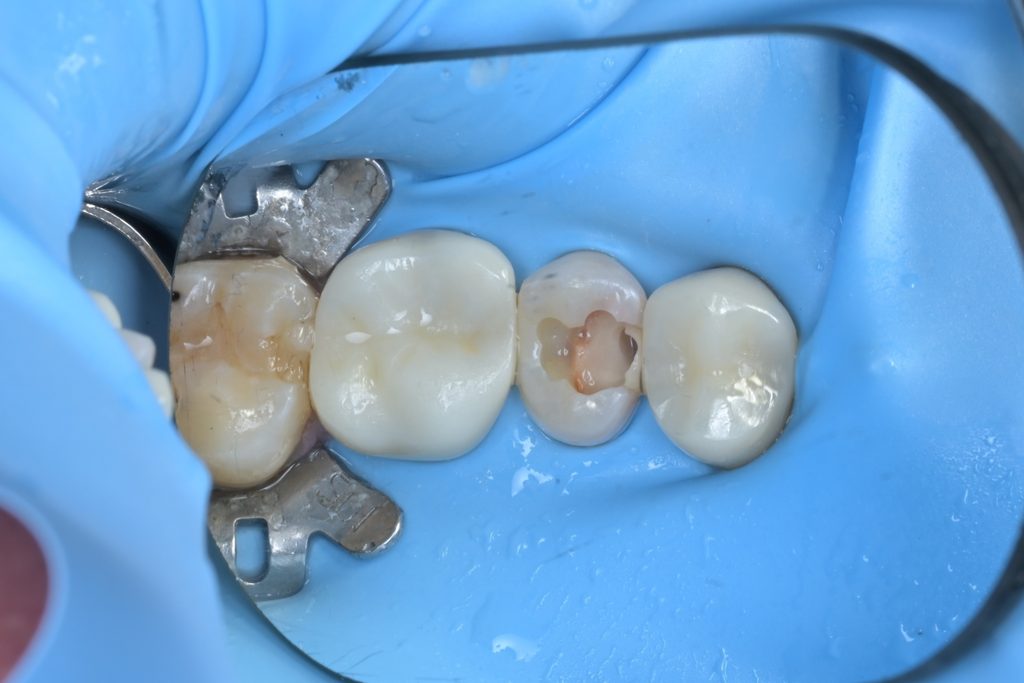

Step 3: 치수 노출 확인 및 평가

우식을 완전히 제거하는 과정에서 치수가 노출되었습니다. 이 시점에서 치수의 생활력과 건강도를 평가하는 것이 중요합니다.

출혈이 선홍색이고 지혈이 가능한 상태였으며, 환자분도 자발통이 없었기에 생활치수치료(VPT)를 진행하기로 결정했습니다.

Step 4: MTA를 이용한 치수 보호

노출된 치수 부위를 생리식염수로 세척하고, 지혈을 확인한 후 MTA(Mineral Trioxide Aggregate)를 치수 노출 부위에 직접 접촉시켜 밀폐합니다. MTA는 수분이 있는 환경에서도 경화되며, 치수 조직과 생체적합성이 우수하여 상아질 브릿지 형성을 유도합니다.